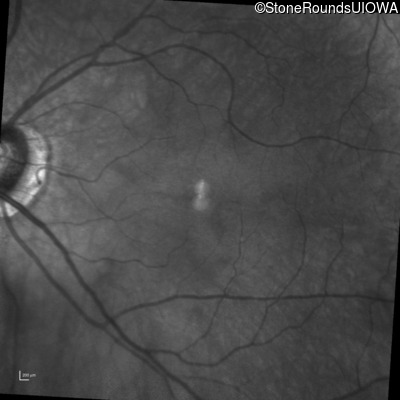

Infrared Fundus Photograph - Right - 20/200

Exemplar